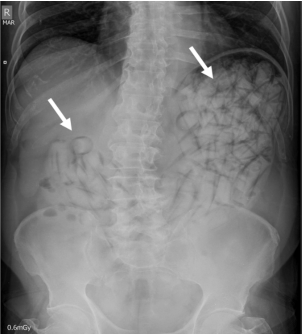

La radiografía de abdomen al ingreso mostró múltiples imágenes radiopacas en el marco cólico sugestivas de cuerpos extraños (Figura 1). Se solicitó una tomografía computarizada (TC) de abdomen con contraste en la cual se describieron hallazgos compatibles con síndrome pilórico secundario a retención gástrica de cuerpos extraños, sin evidencia de tránsito hacia distal (Figura 2). Fue llevado a laparotomía exploratoria identificando marcada distensión de la cámara gástrica; se realizó una gastrotomía y extracción sin complicaciones de 97 cuerpos extraños de látex en forma de dedo con pérdida del recubrimiento de parafina (Figura 3).

La radiografía simple es la herramienta más importante para la detección, con una sensibilidad entre 40-90 % dependiendo del tipo y pureza de la droga, material del paquete, tamaño, localización y número de paquetes 1,5,7; la especificidad puede ser tan alta como del 97 % 5. Los signos radiográficos que pueden identificarse incluyen: múltiples cuerpos extraños radiopacos y signos de “doble condón”, “tic tac”, paralelismo, envoltura hiperdensa o multiplicidad de cuerpos extraños con aire atrapado entre ellos 1,4,5.